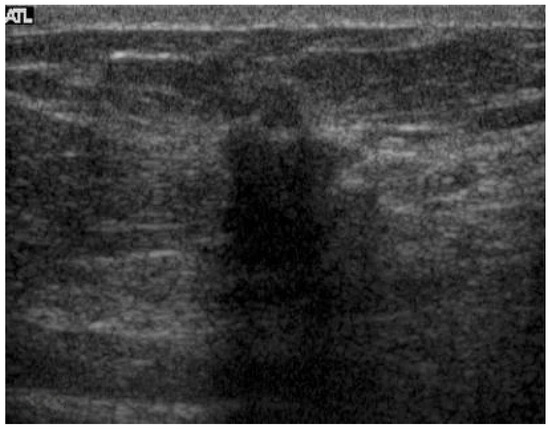

Advances in Medical Image Processing for Early Breast Cancer Detection: Classical Techniques and Deep Learning Perspectives

Breast cancer is the most common malignancy among women and a leading cause of cancer-related mortality, making early and accurate detection essential. This review summarises advances in breast imaging and computational diagnostics across mammography, ultrasound, and magnetic resonance imaging (MRI), highlighting challenges in differentiating benign from malignant lesions and identifying rarer tumour types. Key preprocessing steps—denoising, deblurring, and contrast enhancement—are reviewed as they improve image quality prior to analysis. Classical methods (e.g., thresholding, edge detection, and region growing) are compared with deep learning approaches for segmentation and classification. CNNs, RNNs, and emerging transformer-based models consistently outperform handcrafted pipelines, with representative studies reporting 5–15% gains in AUC/accuracy and deep models achieving AUC > 0.85–0.95 on several benchmarks. The review also discusses dataset constraints, common evaluation metrics (AUC, Dice, sensitivity, specificity), and clinical translation barriers such as interpretability and domain shift. Overall, AI-driven methods show strong potential to enhance early detection and support improved breast cancer outcomes. Full article

Show Figures

Figure 1